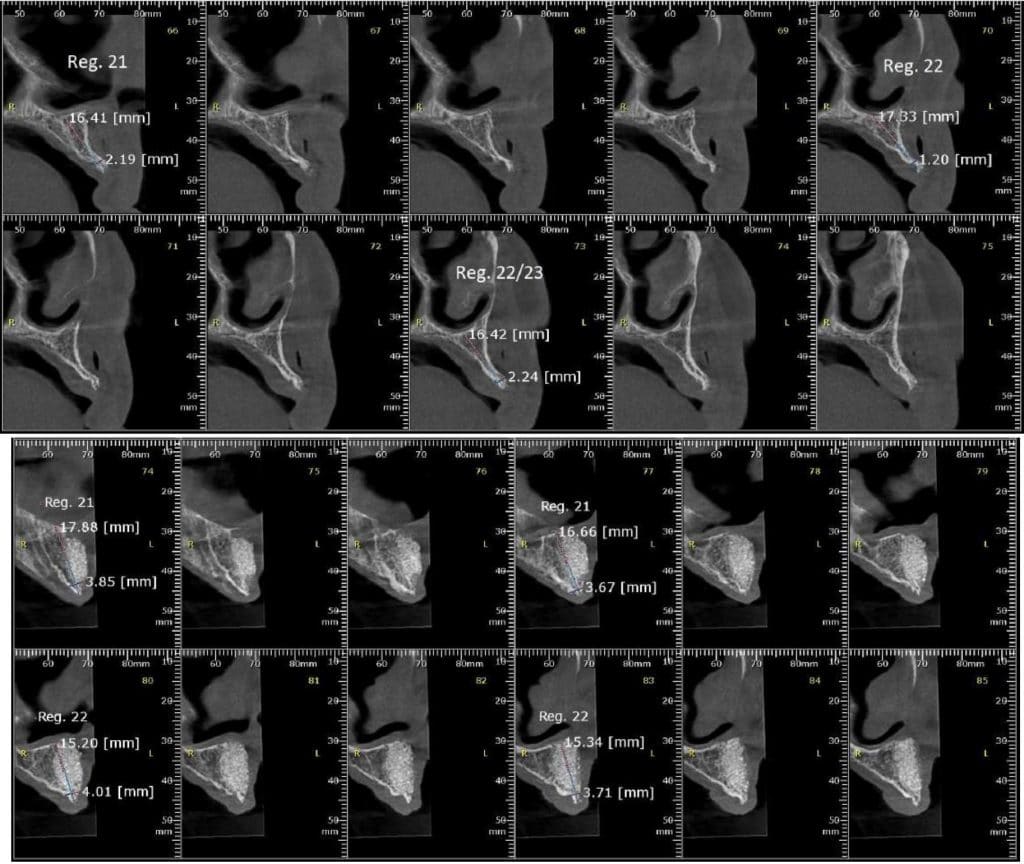

Olá colegas, aqui está um caso didático de reconstrução óssea total da maxila, levantamento do seio maxilar bilateral e bloqueio espesso com aplicação do conceito de PRF e Biotensigrity.

Após 6 meses de maturação óssea e implantes instalados com torque médio de 35 N / cm2.